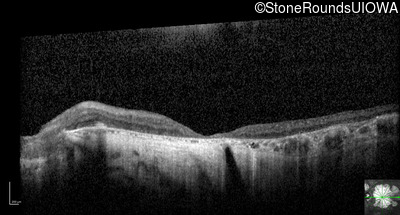

Optical Coherence Tomography - Right - 20/300

Exemplar / OCT Stack

OCT Stack